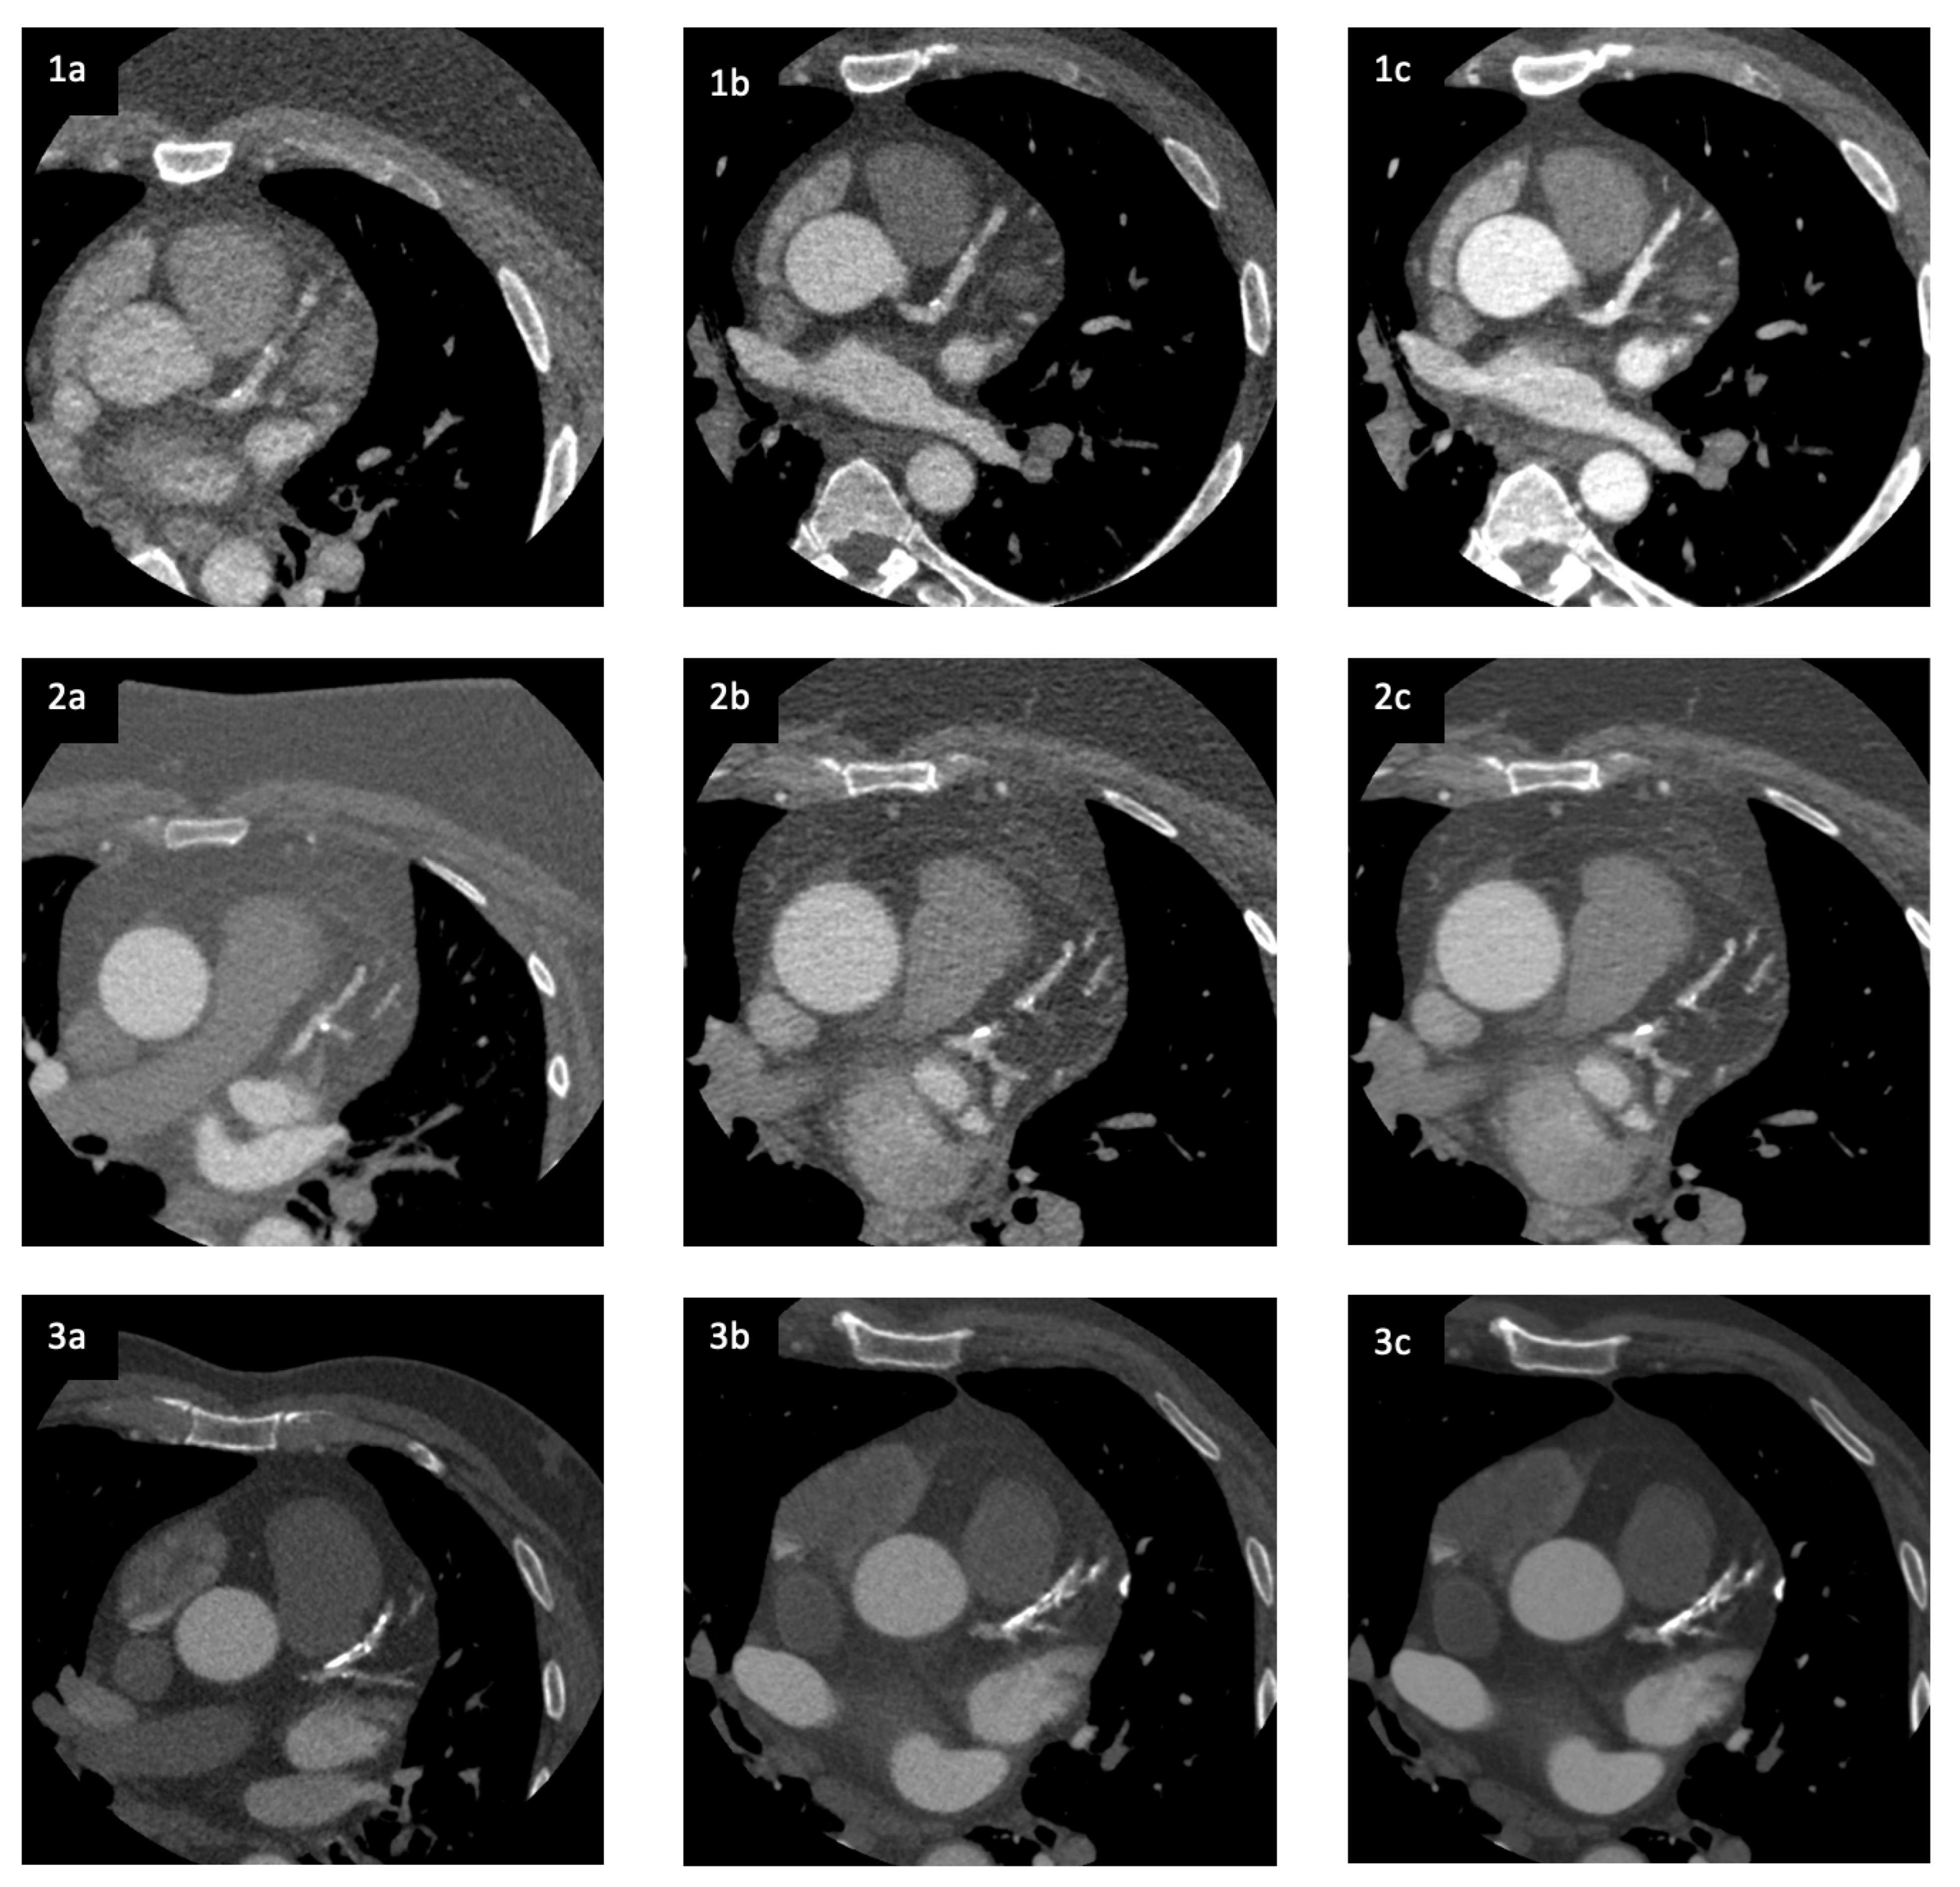

3.2. Image Quality and Diagnostic Accuracy

| Image Quality Criteria | CT Scanner and Reconstruction Method | Odds Ratio [95% CI] | p-Value |

|---|---|---|---|

| 1. Sharp/clear delineation of the aortic wall | Revolution CT ASiR-V [ref.] | ||

| Revolution Apex ASiR-V | 1.86 [0.66–5.21] | 0.24 | |

| Revolution Apex DLIR | 1.51 [0.71–3.24] | 0.29 | |

| 2. Visually sharp delineation of the vessel wall of LAD | Revolution CT ASiR-V [ref.] | ||

| Revolution Apex ASiR-V | 0.76 [0.31–1.85] | 0.55 | |

| Revolution Apex DLIR | 3.30 [1.64–6.54] | 0.001 | |

| 3. Visually sharp delineation of the vessel wall of RCA | Revolution CT ASiR-V [ref.] | ||

| Revolution Apex ASiR-V | 1.05 [0.44–2.46] | 0.92 | |

| Revolution Apex DLIR | 1.76 [0.85–3.64] | 0.13 | |

| 4. Visually sharp delineation of the vessel wall of CX | Revolution CT ASiR-V [ref.] | ||

| Revolution Apex ASiR-V | 1.96 [0.78–4.96] | 0.15 | |

| Revolution Apex DLIR | 1.31 [0.63–2.72] | 0.48 | |

| 5. Visualization of the myocardial septum between the right and left ventricle | Revolution CT ASiR-V [ref.] | ||

| Revolution Apex ASiR-V | 0.66 [0.20–2.14] | 0.49 | |

| Revolution Apex DLIR | 4.82 [1.60–14.56] | 0.005 | |

| 6. Homogeneity in the left/right ventricle | Revolution CT ASiR-V [ref.] | ||

| Revolution Apex DLIR | 3.26 [1.34–7.91] | 0.009 | |

| 7. Overall image quality | Revolution CT ASiR-V [ref.] | ||

| Revolution Apex ASiR-V | 0.999 [0.80–1.25] | 0.995 | |

| Revolution Apex DLIR | 1.23 [1.04–1.46] | 0.017 |